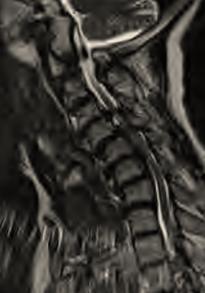

https://upload.orthobullets.com/topic/2031/images/mri-cervical-sag-t2 - shows mild spinal stenosis with cord compression.bmp

• MRI

• indications

• study of choice to evaluate degree of spinal cord and nerve root compression

• findings

• effacement of CSF indicates functional stenosis

• spinal cord signal changes

• bright signal on T2 images (myelomalacia)

• signal changes on T1-weighted images correlate with a poorer prognosis following surgical decompression

• compression ratio of <0.4 carries poor prognosis

• CR = smallest AP diameter of cord / largest transverse diameter of cord